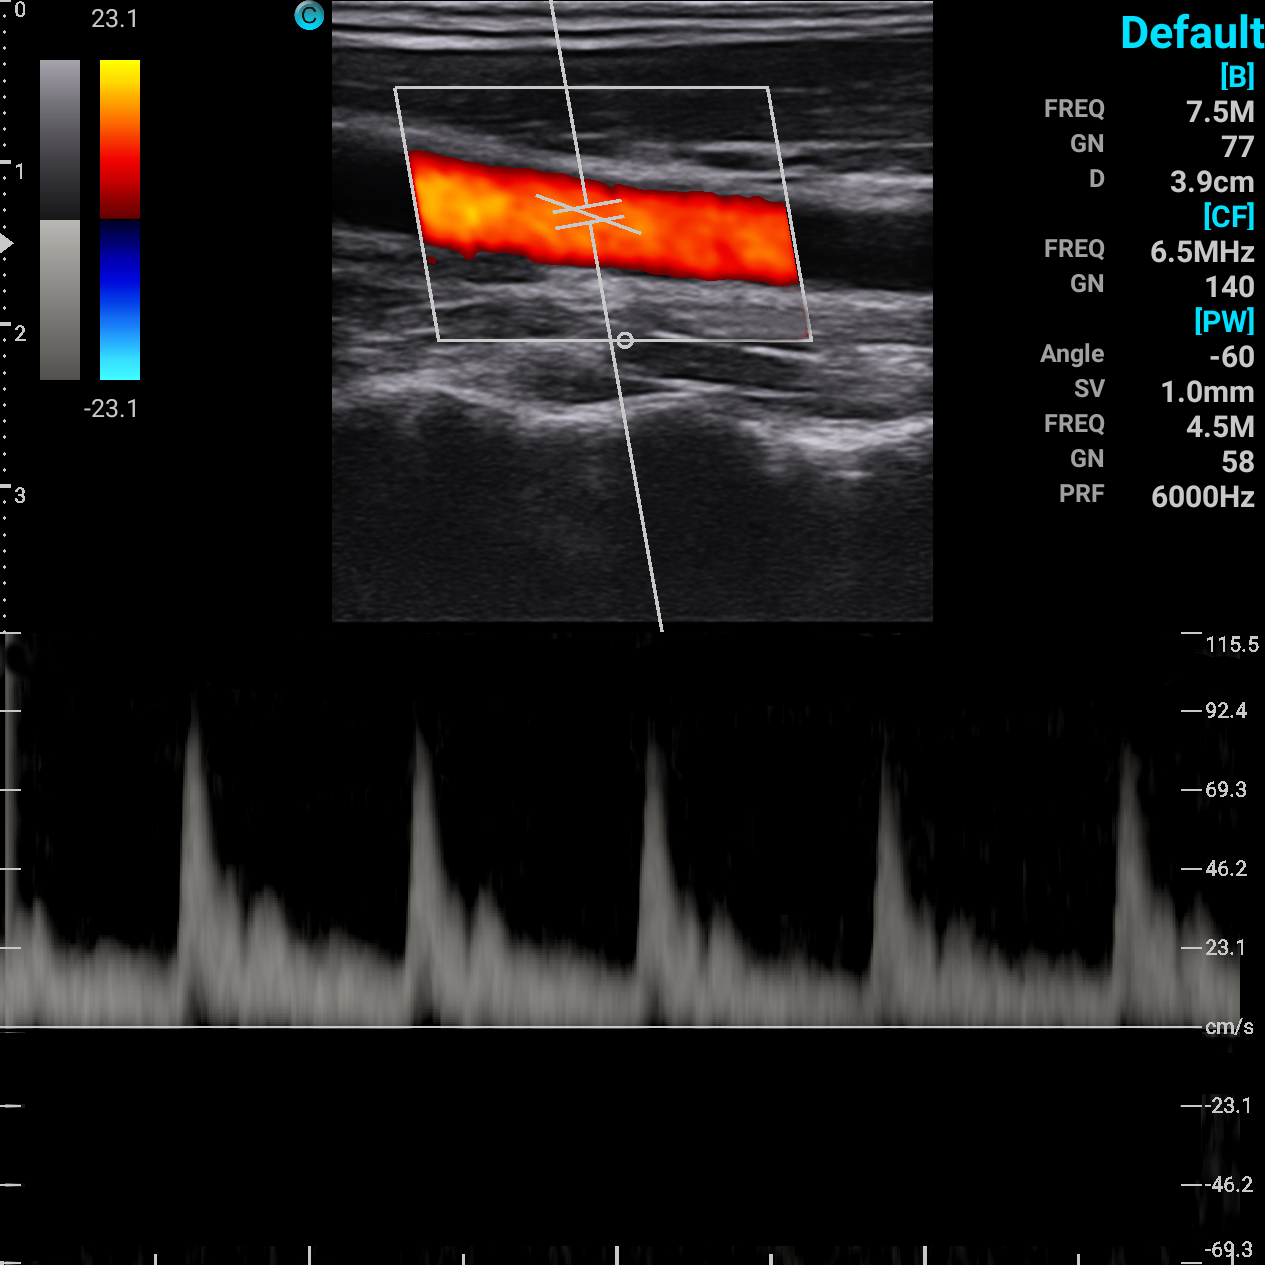

颈动脉 PW模式